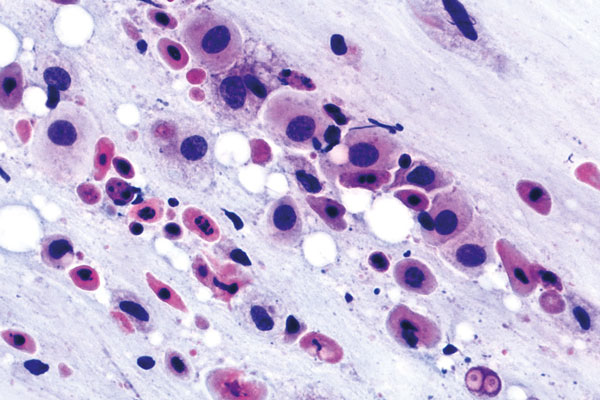

Februar

richtige Antwort:

c. Adenokarzinom des Endometrium (V-e)

- deutlich größere Zellen als bei normalem Endometrium

- Tumordiathese im Hintergrund mit frischen und zerfallenen Ery’s

- Mit zunehmender Entdifferenzierung nimmt die Zell- und Kerngröße zu

- Deutliche Anisonukleose